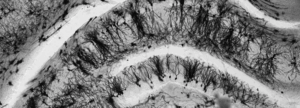

Neurociencias